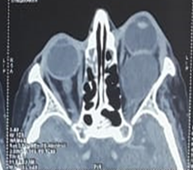

Imaging (CT and MRI)

revealed a 35 x 28 x 27 mm left extraconical cystic formation pushing back a

deformed globe, the muscular cone and the lacrimal gland with grade III

exophthalmos and optic nerve stretch (Figures

2 and 3).

Figure 2. Orbital CT scan showing a well-limited

extra conical formation with regular contours and non-enhanced liquid density

after injection of contrast medium measuring 30 x 26 mm extended over the eye.